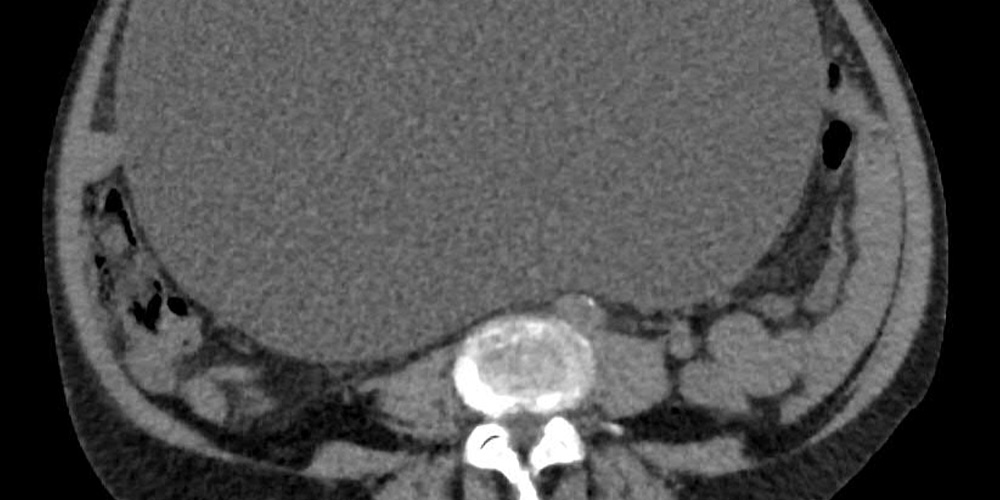

Die Diagnose im Klinikum Klagenfurt lautete auf Eierstockkrebs im Frühstadium. Die Entfernung des 10,2 Kilogramm schweren und im Durchmesser 30 Zentimeter großen Tumors verlief ohne Probleme: “Die Patientin benötigt weder eine Chemotherapie noch eine Strahlentherapie”, erklärte Reinhard Mittermair, der Abteilungsvorstand der Allgemein- und Viszeralchirurgie am Klinikum Klagenfurt.